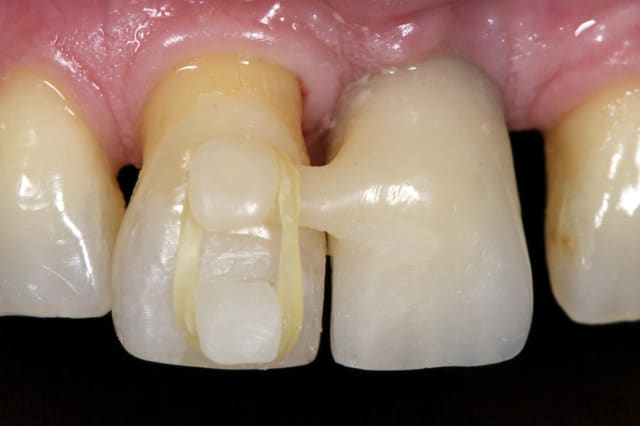

Merci jt2000, seespan et inset pour votre aide. Voici finalement le dispositif que l'on a choisi car je voulais me servir de l'implant comme ancrage.

je vous montrerai l'evolution, favorable ou.... défavorable.

je suis a l'écoute des ortho pour leurs conseils et critiques...

A virskn - Eugenol

B c15bbz - Eugenol

C abqhrm - Eugenol